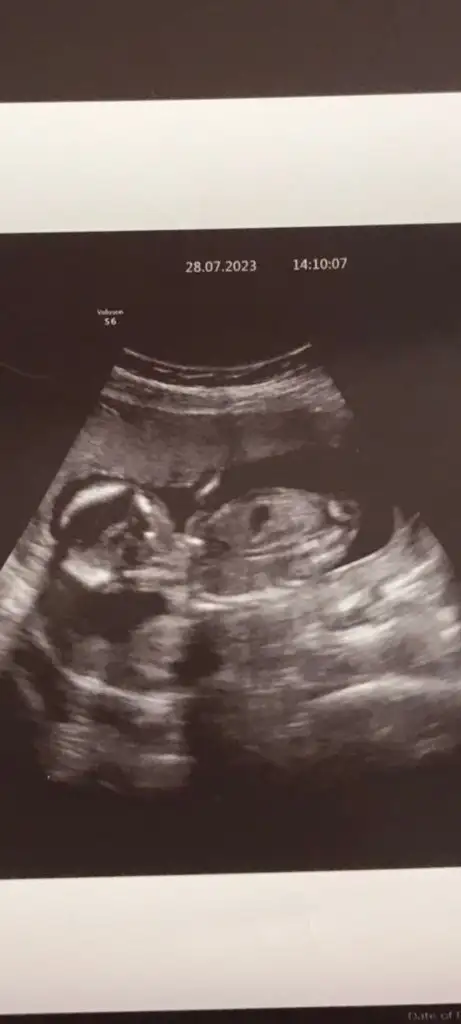

Bana da tahminde bulunurmusunuz lütfen 💓❤️bastakıler 9+2 sondaki 10+2 haftalık

Merhabalar cinsiyet tahmini yapar mısınız

• 1D469D25-CF44-4E74-AEF4-C558DB2C0204.webp

1D469D25-CF44-4E74-AEF4-C558DB2C0204.webp

23,7 KB · Görüntüleme: 85

• DB85050B-D3F1-46D7-943D-968259AB6E65.webp

DB85050B-D3F1-46D7-943D-968259AB6E65.webp

30,8 KB · Görüntüleme: 67